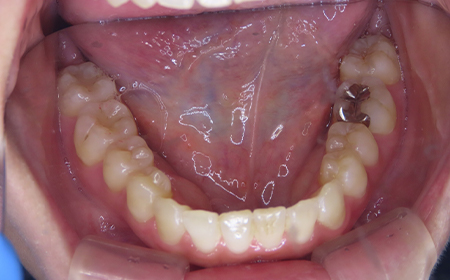

CASE08

Before

After

| 施術名 |

インビザラインコンプリヘンシブを用いた矯正治療(叢生) |

| 治療期間 |

1年 |

| 治療費 |

880,000円(税込) |

| リスク |

マウスピース装置により疼痛・咬合時痛を生じる事があります。割れたり壊れたりする事があります。 |

歯科医師からのコメント

「上顎八重歯が気になる」で来院されました。分析すると、軽度なねじれでしたのでインビザラインGoにて治療をすすめていきました。マウスピースを積極的に使用し、順調に治療がすすんでいきました。仕上がりにとても満足しておられました。